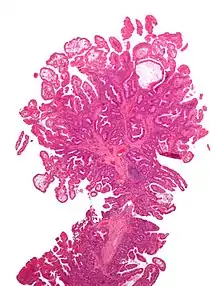

| Juvenile Polyp | Upper GI tract and colon | Cystically dilated glands with expanded lamina propria | Not inherently, may develop dysplasia |  |